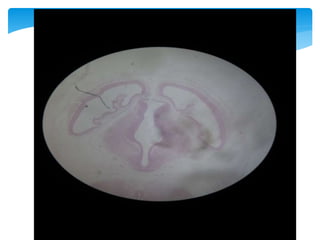

HEMISFERIOS CEREBRALES

26

Palio

Ventriculo

Lateral

Piamadre